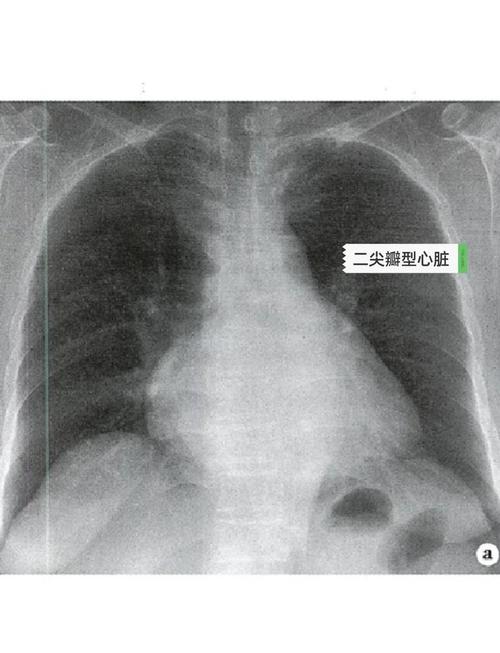

当医生在X光片上看到这个肺动脉段的弧度变得异常圆钝、饱满,甚至形成一个凸出的角度时,就称为“肺动脉段突出”,这本身不是一个疾病,而是一个影像学上的体征,它提示我们可能存在某些病理情况。

肺动脉段突出是右心室压力负荷增加或血流量增加的一个X线表现。

这种血流动力学变化直接反映在X光片上,就是肺动脉血流量增加导致其主干扩张,从而在X光片上表现为“肺动脉段突出”。